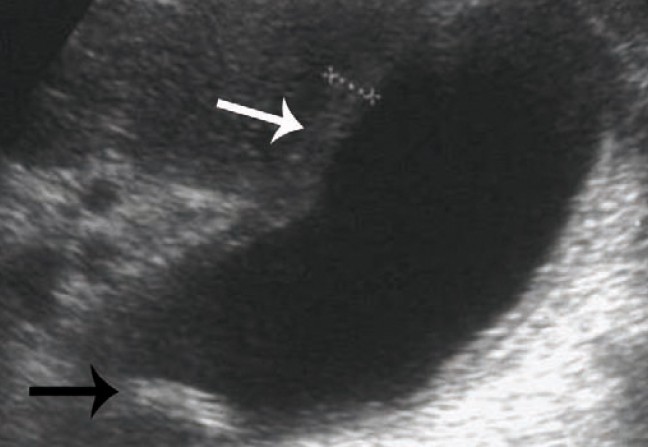

L’échotomographie abdominale est l’examen de choix pour le diagnostic initial. Sa sensibilité et sa spécificité sont supérieures à 98 % pour les calculs de plus de 2 mm. En cas de cholécystite, l’image caractéristique est un épaississement de la paroi vésiculaire. Le passage de la sonde est douloureux (signe de Murphy).

Le diagnostic de lithiase de la VBP repose sur des arguments clinico-biologiques et des examens morphologiques. La lithiase est en effet souvent associée à une augmentation transitoire des transaminases et à une hyperleucocytose. La sensibilité de l’échotomographie est nettement moins bonne pour la lithiase de la VBP (20 à 50 %) que pour la lithiase vésiculaire. La tomodensitométrie a une sensibilité un peu plus élevée, de l’ordre de 50 à 75 %. L’échoendoscopie a une très bonne sensibilité, mais elle nécessite une anesthésie générale. Le meilleur examen non invasif est actuellement la cholangio-IRM, dont la sensibilité est de 75 à 100 %. La cholangiographie peropératoire est effectuée dès lors qu’il existe une suspicion de calcul de la VBP et que le traitement chirurgical de ce calcul est possible. -